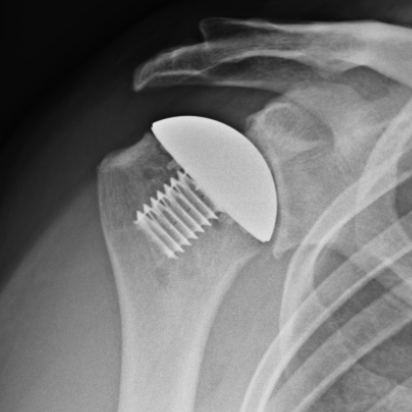

David had a shoulder hemiarthroplasty in November of 2023. Remembering from his previous experience shoulder surgery that he had lengthy recovery ahead, David was amazed how much better he felt in just 2 weeks after his surgery. Below David shares his recovery: